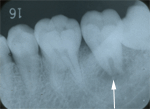

1.初診時

「しみる」ということでしたが、この時はまだ、原因歯を特定できませんでした。 |

2.2ヵ月後

ひどく腫れてきましたが、大きな虫歯は見あたりません。

歯周病による逆行性歯髄炎が疑われました。 |

3.3ヵ月後

神経の治療をしました。(白矢印の歯) |